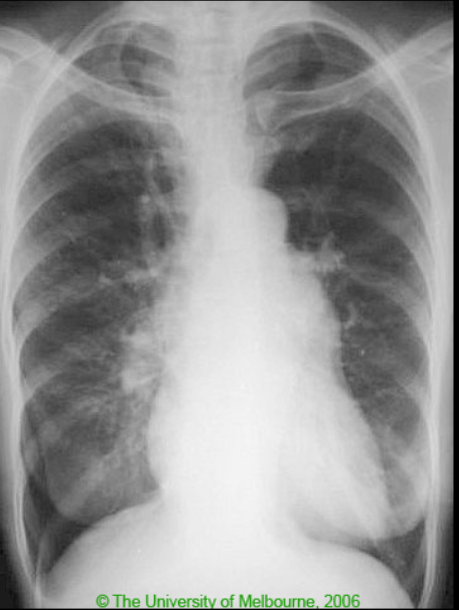

33yo female presents with dyspnoea on exertion with associated cyanosis and fatigue. On examination she has a loud P2. Over the following years, she goes on to develop RVF

Pulmonary HTN

Causes: idiopathic (primary), PE, COPD, ILD, LVF, connective tissue disease, portal hypertension